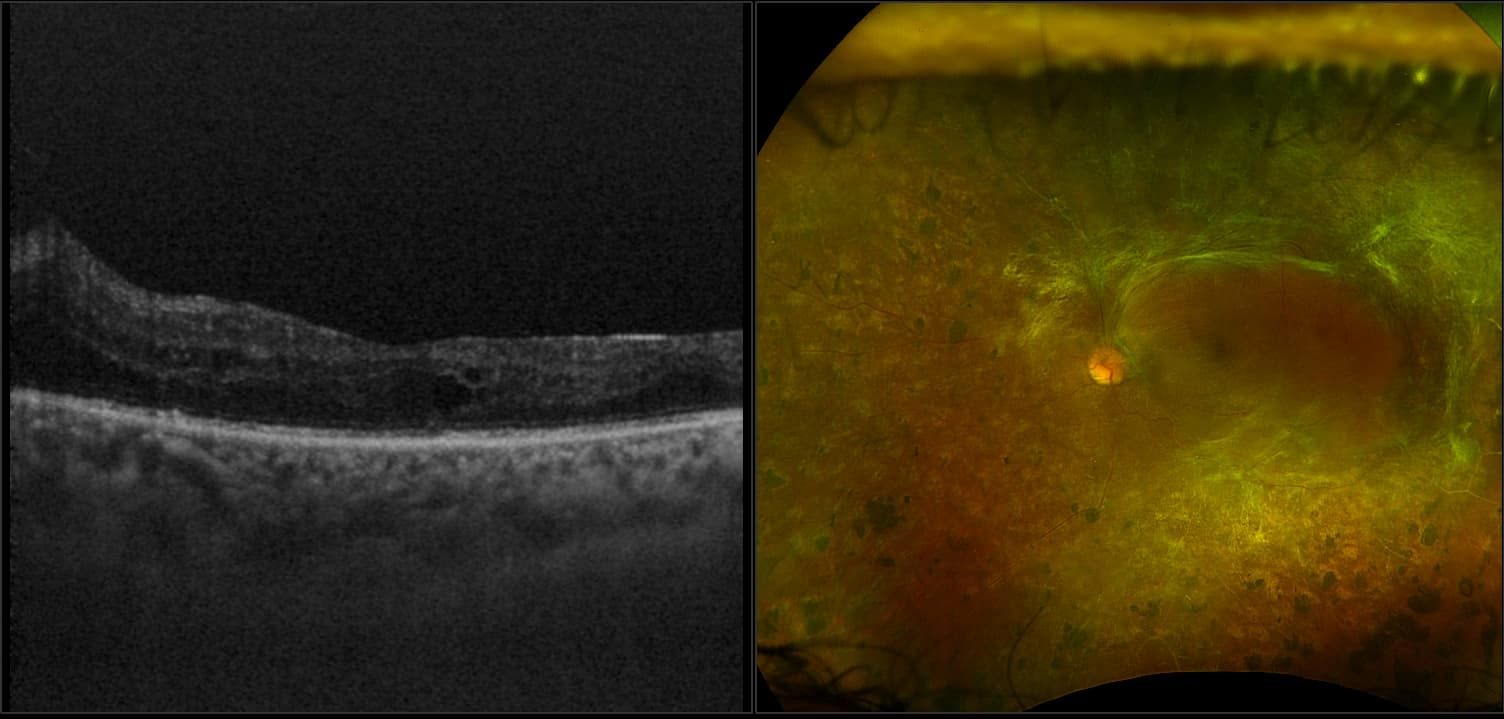

optomap fa Key Indicator to Predict the Progression of PDR

Research using optomap fa reveals that 50% of eyes with baseline PPL are at high risk for DR.

optomap Multimodal Diabetic Eye Disease Cases

Optos offers multimodal imaging with all ultra-widefield devices. Having both ultra-widefield and four images captured in less than one second has been shown to enhance pathology detection and disease management as well as improve practice and clinic flow. Ultra-widefield multimodal imaging is important across all access points of patient care - screening, detection, diagnosis, and treatment.